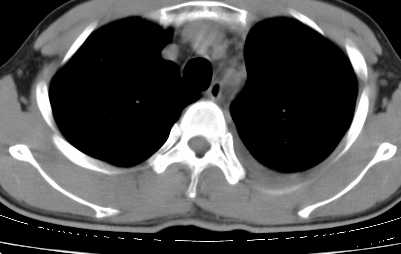

二周前患者无明显诱因出现咳嗽,多为刺激性干嗽,无咯血,伴心悸,低热,夜间无明显盗汗,消瘦明显

年龄?左侧胸腔中量积液,左下肺见有较多斑片状和大片状影,伴有支气管充气征,考虑:1、左下肺炎;2、结核。肿瘤可以基本排除。

考虑:1、左下肺结核左侧胸腔中量积液,心包积液纵隔肿大淋巴结.

考虑:1、左侧中量胸腔积液伴左肺下叶肺膨胀不全、炎症。

2、心包积液。

左下肺见有较多斑片状和大片状影,支气管通畅,左侧胸腔积液,考虑:左下肺炎伴胸腔积液

左侧中量胸腔积液伴左肺下叶肺膨胀不全、上肺外围多个小囊样腺泡样病灶。考虑化脓炎症。

心包积液没有,纵隔积液。

纵隔肿大淋巴结不明显。

1、左侧中量胸腔积液伴左肺下叶肺膨胀不全、。

3 无纵隔肿大淋巴结.

患者刺激性干嗽,无咯血,伴心悸,低热,夜间无明显盗汗,消瘦明显,左侧中量胸腔积液伴左肺下叶肺膨胀不全、上肺外围多个小斑片病灶。考虑肺结核可能性大。

左肺舌叶及下叶见斑片状,大片状高密度影并相应处胸膜及心包不规则增厚,左肺下叶膨胀不全。右肺未见异常,双肺段以上支气管通畅。纵隔左移,其内未见明显肿大淋巴结。左侧胸腔积液。

1.考虑:左肺化脓性炎症。2.左侧胸腔积液(中等量)。3.心包炎症。